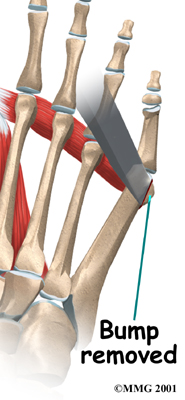

If all else fails, surgery may be recommended to reduce the deformity. Surgery usually involves removing the prominence of bone underneath the bunion to relieve pressure. Surgery may also be done to realign the fifth metatarsal if the foot has splayed.

Bunionette Removal

To remove the prominence, the surgeon makes a small incision in the skin over the bump. The bump is then removed with a small chisel, and the bone edges are smoothed. Once enough bone has been removed, the skin is closed with small stitches.